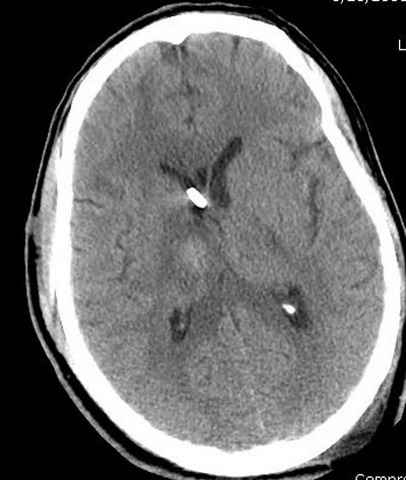

03.14.2005

больному 42, автоавария, политравма, открытая черепномозговая травма, безсознании, открытый перелом бедра, размозжение мягких тканей, дефект кожи на передней поверхности бедра около 13 см2 от ожога, компартмент синдром.

По поводу открытого перелома больной ургентно взят на ретроградное интрамедулярное штифтование, после рутинного дебрайдмента и фасциотомии на бедре и на голени.

Наблюдается службой травмы и нейрохирургии (ICP) Increased Intracranial Pressure by ventricular cateter

монииторинг